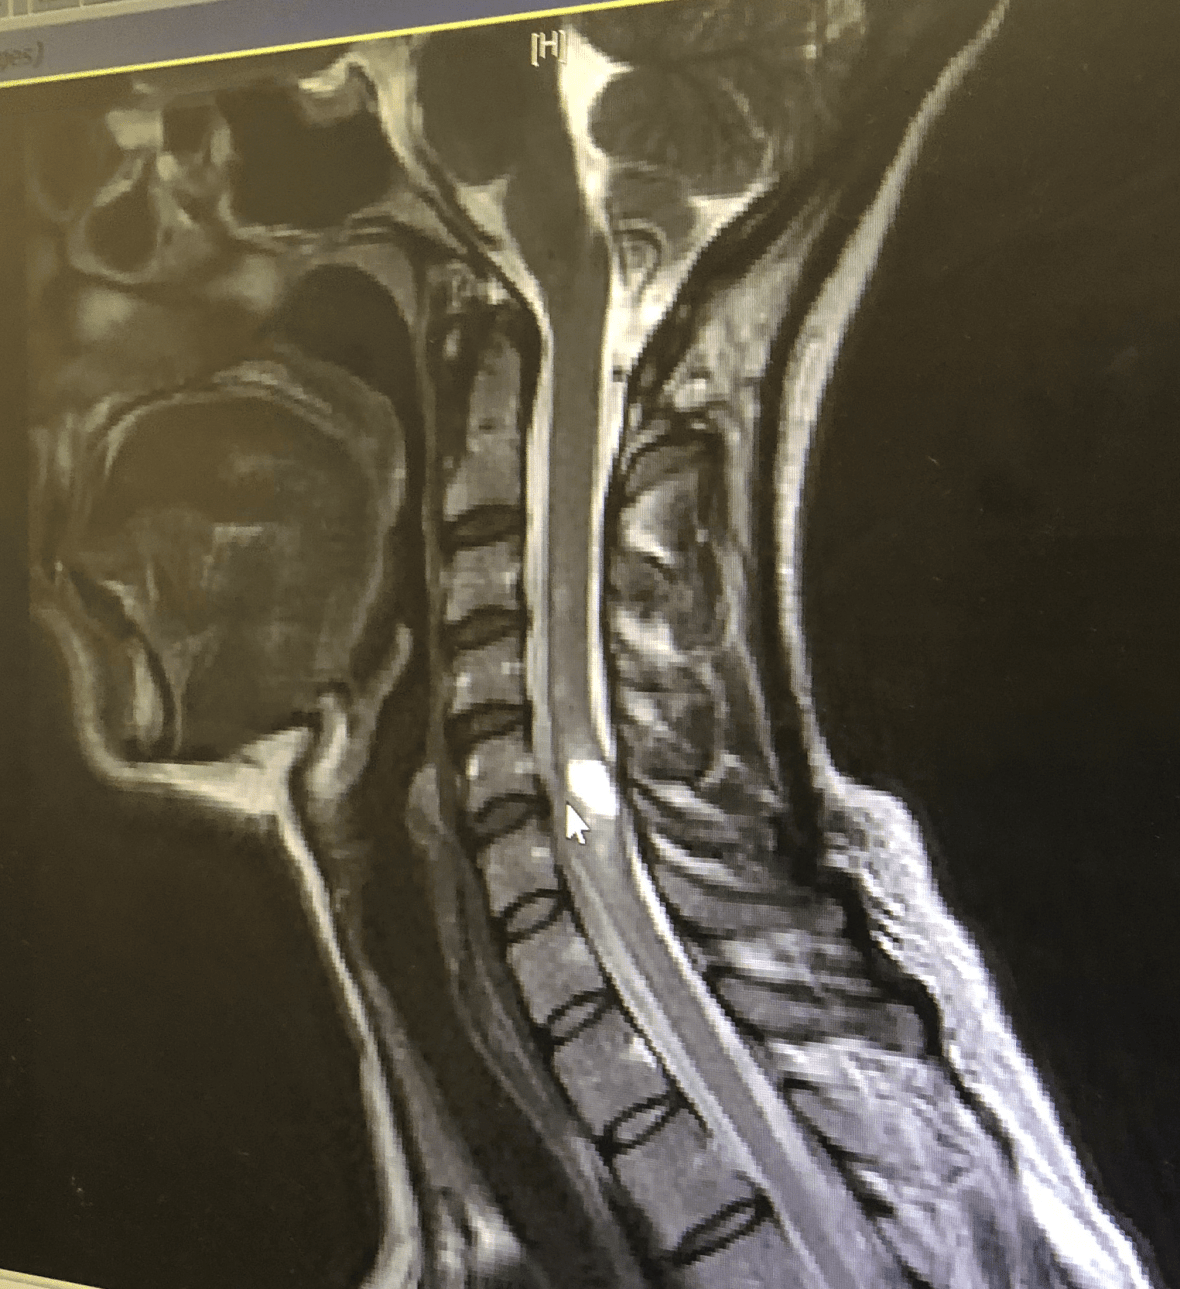

On Sunday, June 24th, 2018, I had a seizure on our kitchen floor, right in front of you while you were playing together with Play-Doh, and was rushed to the hospital in an ambulance. We found out hours later that I have tumors in my brain, ear canal, and spinal cord, and they’re beginning to show symptoms, requiring surgery.